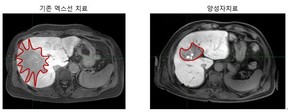

- 간암 극복할 양성자치료, '간암 치료' 효과 탁월

- [환경데일리 김영민 기자]간암 치료 정복이 한 발짝 다가오고 있다.삼성서울병원 암병원 양성자치료센터(센터장 표홍렬)가 본격 가동 1년만에 치료환자수 500명, 연간 치료건수 9000건을 넘어섰다. 이는 비슷한 시기에 오픈한 다른 국가 ...